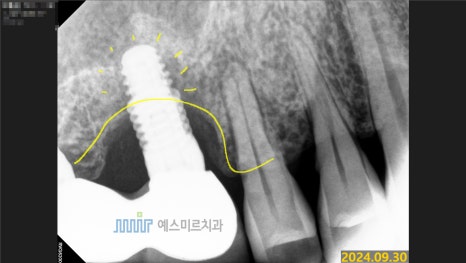

정밀 촬영과 검진 결과,

기존 임플란트 픽스처(뿌리)에 염증이 함께 발생한 상태였고

주변 골 손실도 상당해 제거 및 재수술이 필요한 상황이었습니다.

이번 케이스는 임플란트 픽스처 주변 염증으로 뼈손실이 있었기 때문에

특수 제거 키트인 ‘메가젠 맥가이버 키트’를 사용하여

주변 뼈 손상을 최소화하면서 안전하게 제거를 진행했습니다.